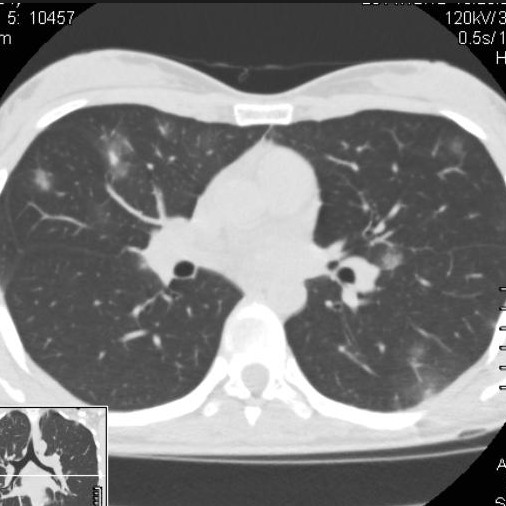

Виды КТ исследований внутренних органов включают в себя сканирование грудной клетки, брюшной полости и забрюшинного пространства, области малого таза. Исследование показывает последствия травм внутренних органов, выявляет объемные образования, очаги туберкулеза, пневмонии, механическую желтуху, лимфомы, лимфоденопатии, гемангиому печени и прочее.

Если говорить о картине пневмонии на КТ-снимках, то для каждого вида заболевания характерны свои изменения на изображениях. Бактериальная пневмония на КТ выглядит как поражение нижних долей легких с уплотнением. Воспалительный инфильтрат при поражении легких микоплазмой локализуется диффузно по всей площади органов, также проявляется синдром матового стекла. При вирусной форме пневмонии на снимках визуализируются диффузно расположенные ацинарные области, ослабление или полное отсутствие сосудистого рисунка на ткани легкого, а также верифицируются легочные консолидации и пр.